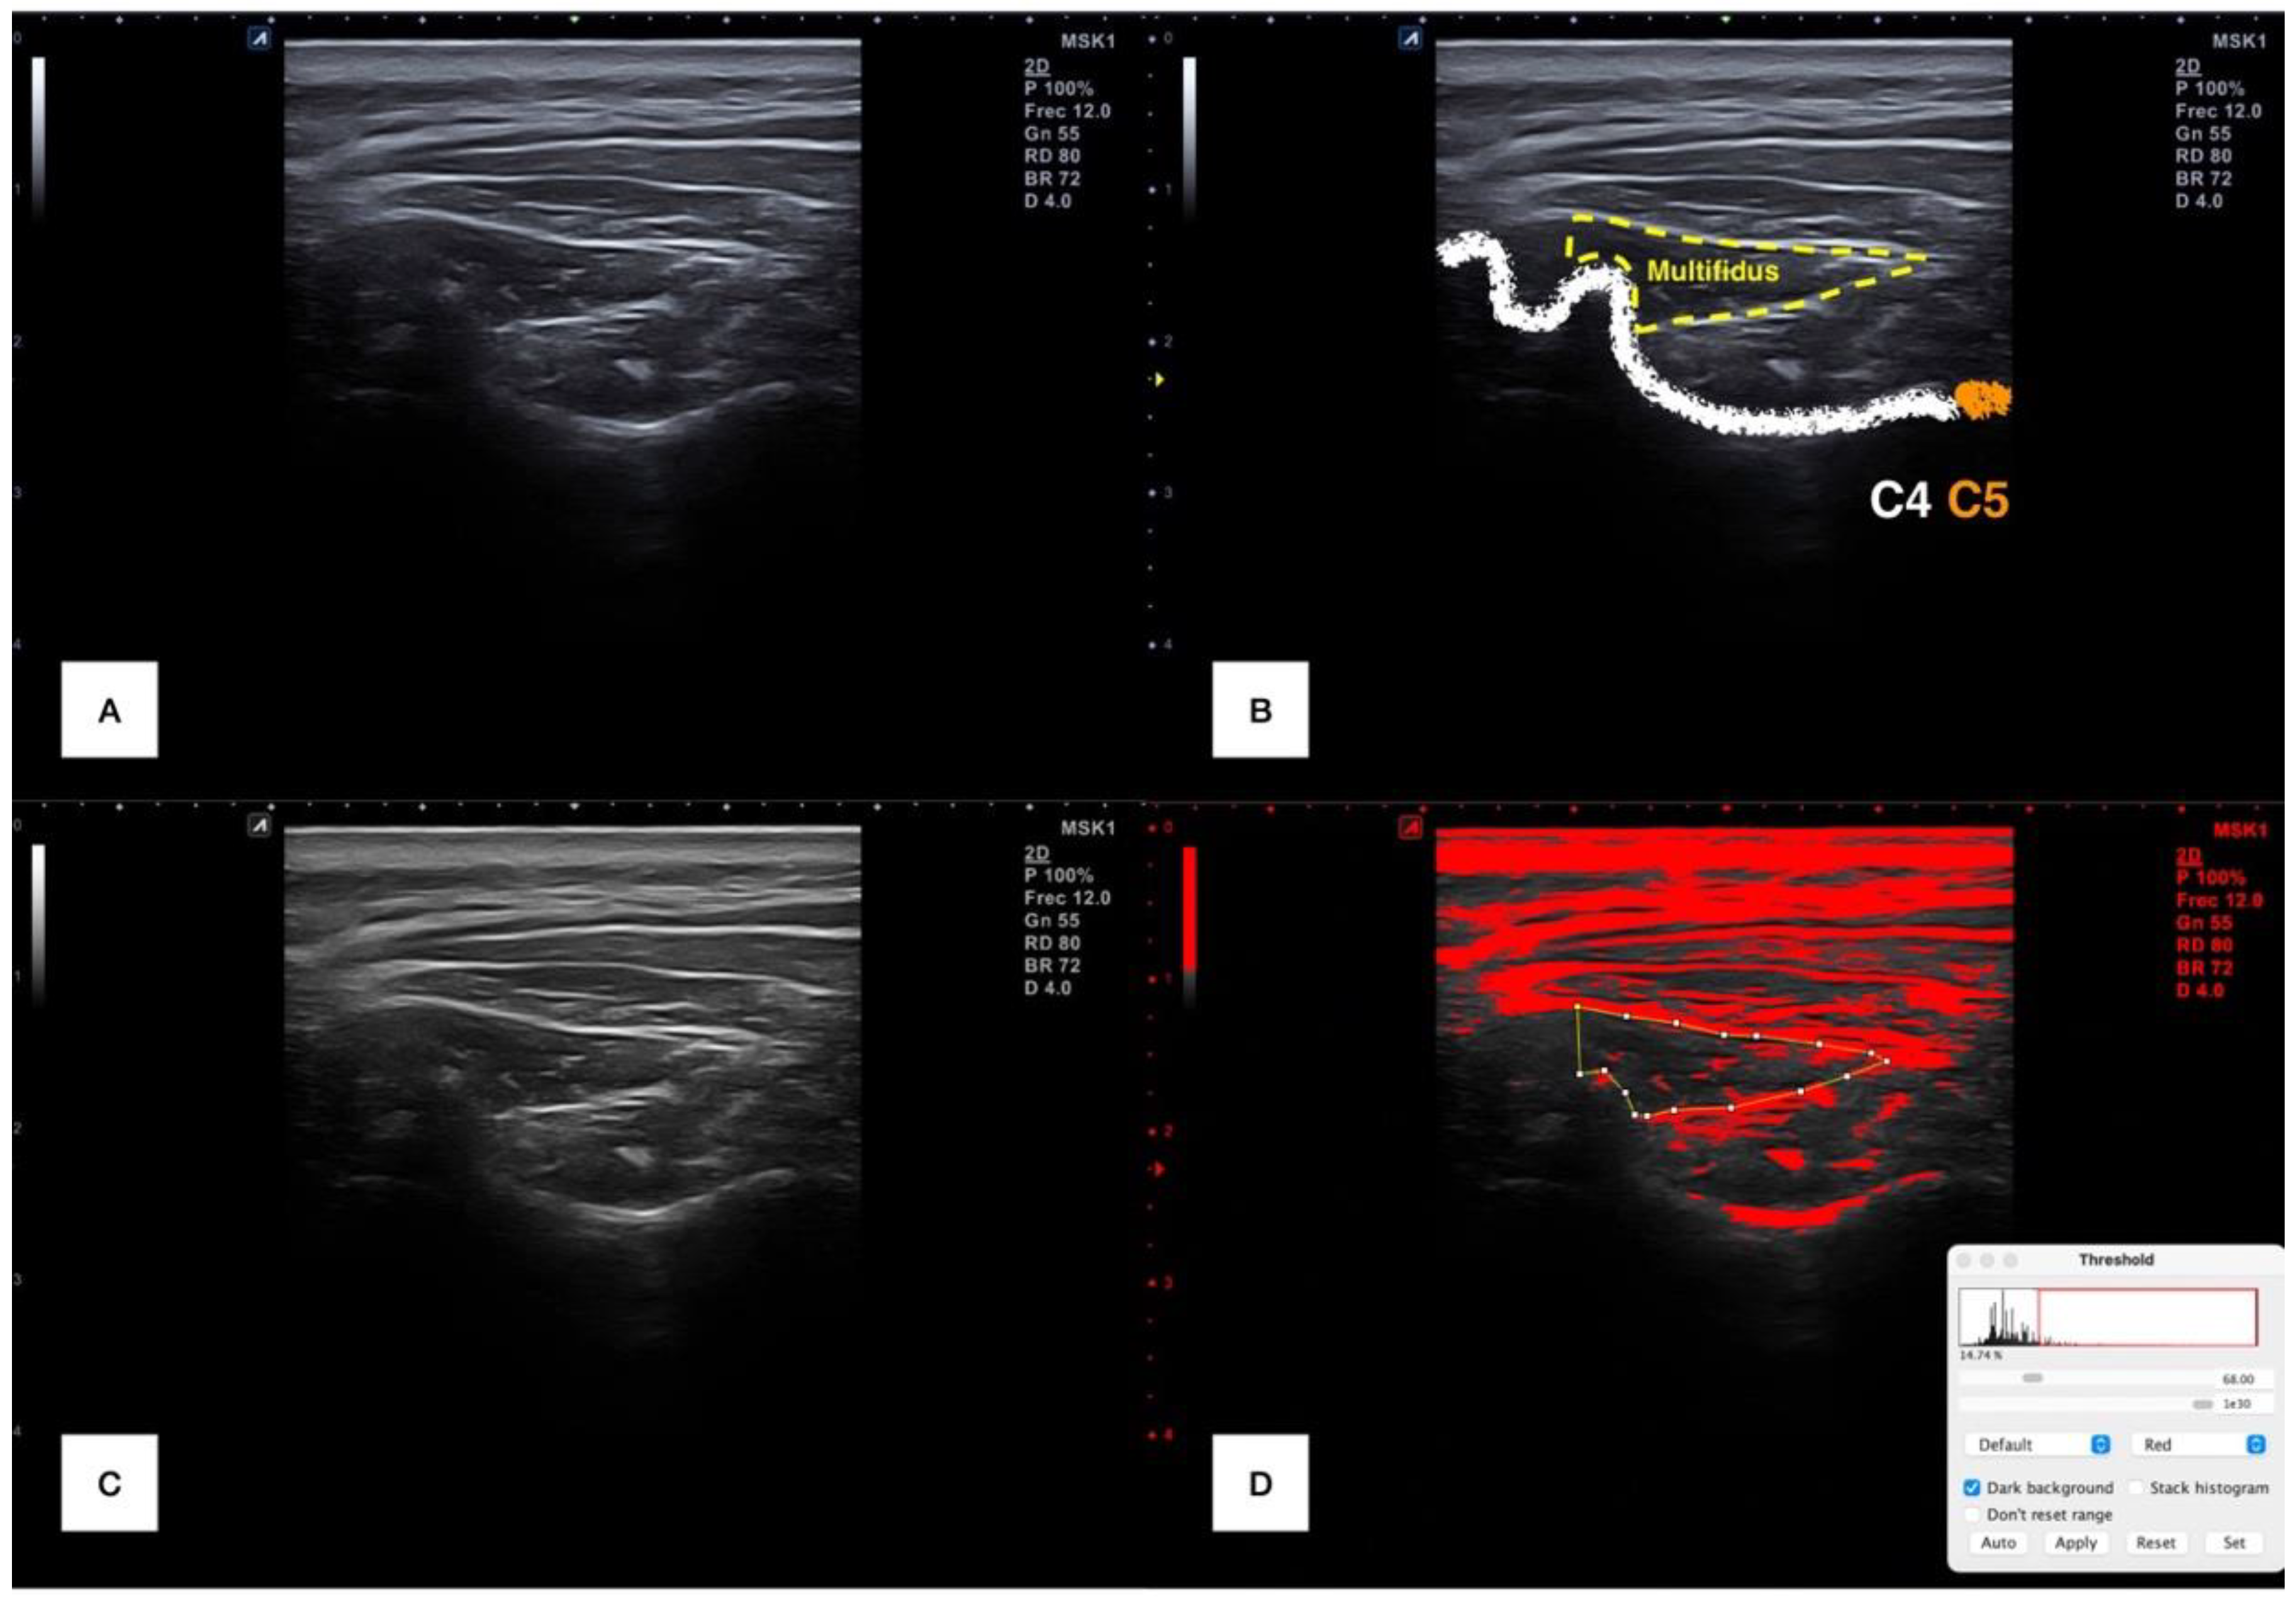

Each examiner transferred in a DICOM format all the files to the ImageJ offline software v.1.42 (National Institutes of Health, Bethesda, MD, USA) and converted from RGB to 32-bit format (256 gray-scale format) for measuring muscle morphology and histology. First, the cervical multifidus was countered within the spinous process of C4 in the medial limit, the internal fascia between the cervical multifidus and short rotators and semispinalis in the bottom and superomedial limit, respectively. Then, a range of brightness was chosen to identify the upper cutoff echo intensity (since intramuscular infiltration is brighter than muscular tissues) for isolating the fatty infiltration, using as a reference the subcutaneous tissue that was set for each image [9,27,29,30]. Finally, muscle cross-sectional area, perimeter, mean echo intensity and fatty infiltration percentage were automatically calculated and collected. This process is illustrated in Figure 1.

Figure 1.

Ultrasound imaging processing. Raw image at C4–C5 level (A); raw image with cervical multifidus muscle delimitation (B); 36-bits image transformation (C) and selection of range of pixels for isolating the intramuscular infiltration (marked in red) (D).